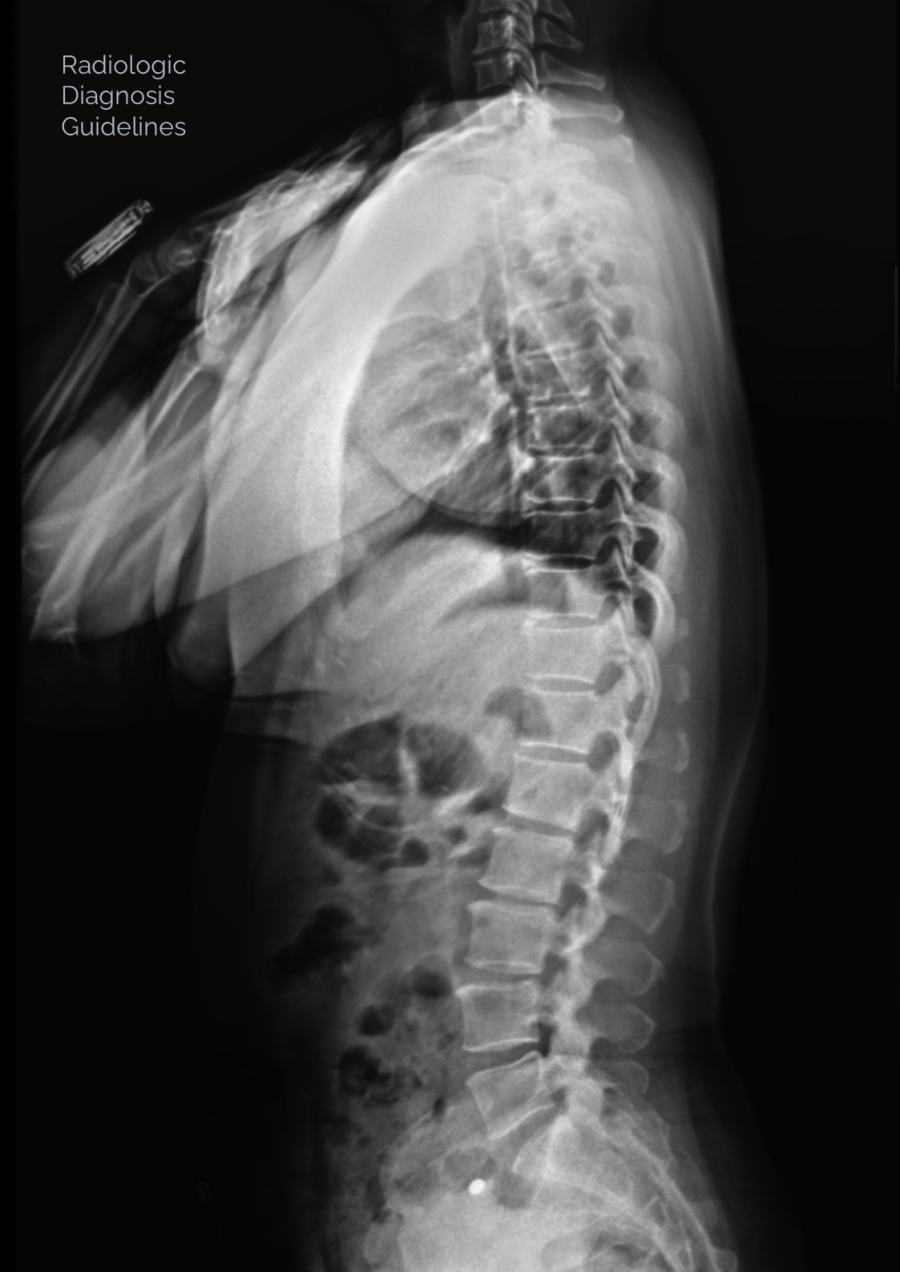

X-ray, All New 2026